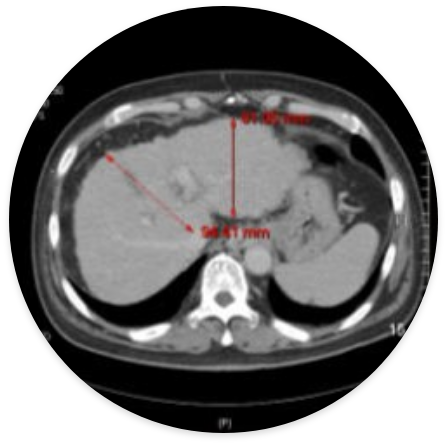

Liver cirrhosis (male 59 years old)-After treatment, hepatocytes are regenerated to increase the size of the liver and soften the liver tissue